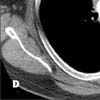

The CT image at the level of the aortic arch confirms the presence of a mass in the anterior mediastinum that displaces the trachea posteriorly (C, arrow). The superior vena cava is not visible; it has probably been compressed or invaded by the large mass. In a second CT image (D), minimally more inferior at the level of the azygous arch, the superior vena cava is again not visible and the azygous vein is densely opacified (arrow).

Figure C

Figure D